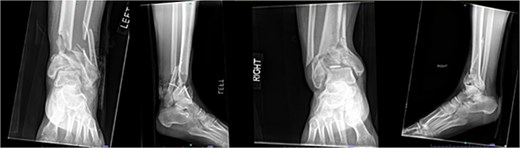

Despite the patient’s noncompliance, he went on to heal uneventfully for the next 2 years until the patient fell from a height of 15 feet, resulting in a left bicondylar tibial plateau fracture and fracture of the left tibial shaft. These injuries required ORIF of his left tibia. Despite the new injury, the hardware from the pilon fractures was in proper alignment (Fig. 4).

Two-year follow-up AP and lateral radiographs of both ankles in patient 2 showing maintained alignment and hardware position.